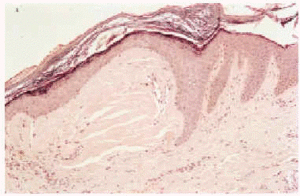

Se realizó una biopsia de una de las pápulas. El estudio histológico mostraba, bajo un revestimiento epidérmico sin alteraciones, lesiones papulosas constituidas por colágena hialinizada escasamente celular con fisuración irregular (fig. 2). La tinción con la coloración de rojo congo resultó negativa, así como la tinción con orceína. Además, el material que constituía la pápula se teñía en azul con la técnica de Masson y con fucsina con la técnica de van Gieson, tal y como corresponde a la colágena. La técnica con anticuerpos anti-CK (anticuerpos anticitoqueratina AE1-AE3) mostró una mínima expresión en la dermis superficial. El diagnóstico realizado fue de pápulas colagénicas auriculares.

Fig. 2.--La dermis papilar se muestra expandida ocupada por un material acidófilo acelular, compacto, resquebrajado tras la fijación (hematoxilina-eosina, x100).